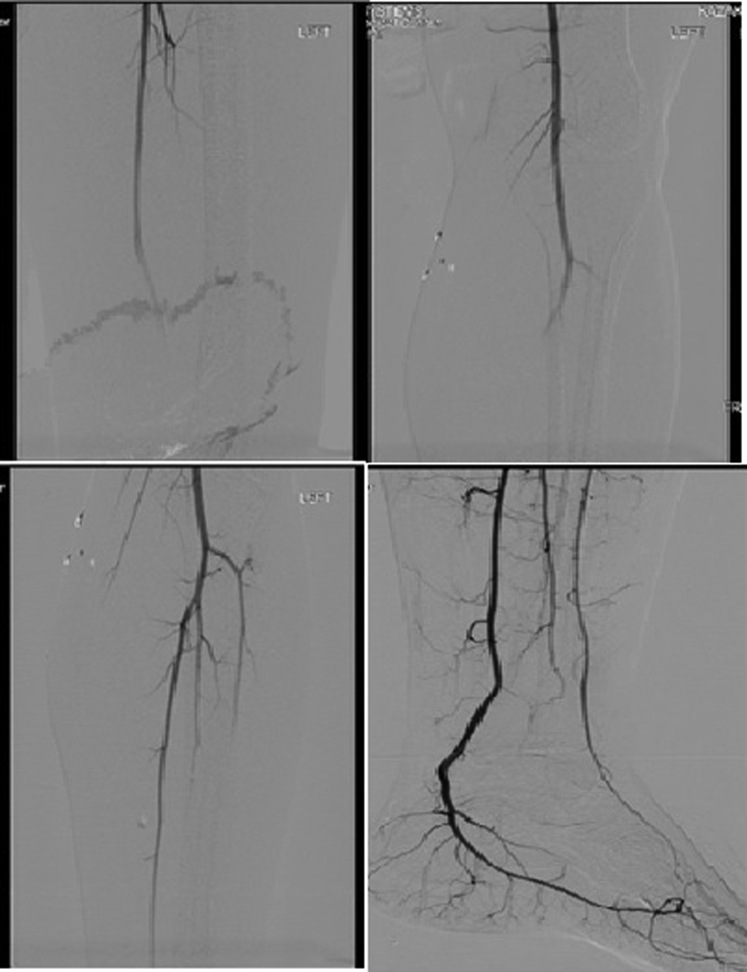

Therapeutic anticoagulation with unfractionated heparin was started, and the patient was taken to the operating room for angiography of the lower extremity and fasciotomy of the left thigh. The angiogram, obtained through a right transfemoral approach, showed no evidence of arterial thrombosis with contiguous sluggish flow down to the foot (Fig 3). The anterior and posterior compartments were found to have elevated pressures. A decompressive fasciotomy of the two compartments was performed through a lateral thigh incision. The muscles of the left thigh compartment appeared healthy, pink, and contractile. Venous duplex ultrasound examination was negative for deep venous thrombosis, and arterial flow was demonstrated to be normal on angiography; thus, viral myositis was suspected in the setting of COVID-19 presentation. However, he was kept on full-dose anticoagulation, given concern for a potential hypercoagulable state. Muscle biopsy specimens obtained were unremarkable.

Fig 3.

Left lower extremity angiogram demonstrating contiguous flow down to the foot.